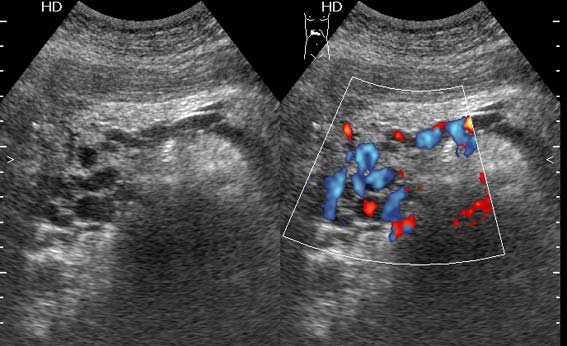

Тромбоз верхней брыжеечной вены

Женщина средних лет, клинический диагноз при поступлении - хронический панкреатит

Я думаю, что все-таки тромбоз селезеночной вены

Верхней брыжеечной

Да, действительно, формирование варикоза в области головки панкреас характерно для тромбоза верхней брыжеечной вены.Брехт писал(а):Верхней брыжеечной

Ургентность здесь относительная, это неострый тромбоз - для развития коллатералей необходимо время. В хирургической клинике при хроническом панкреатите мы нередко видим тромбозы воротной вены, селезеностой вены. Но тромбоз ВБВ встречается нечасто и заподозрить его можно по "гроздьям" варикозов в области головки панкреас. На пилетромбоз обычно указвают "гроздья" варикозов в воротах печени.besliu писал(а):Спасибо за случай,впервые вижу такую патологию,ургентность в поликлинике не так уж частая![]()